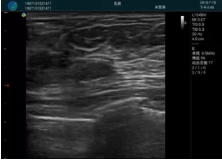

頸動(dòng)脈血流充盈飽滿,無外溢

肝內(nèi)血管顯示清晰,血流敏感無外溢